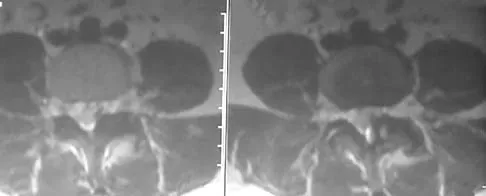

A 40-year-old woman has had sciatic pain on the left side for the past 8 weeks. She reports that the pain radiates to her posterior thigh, lateral calf, and into the dorsum of her left foot. Neurologic examination shows weakness of the left extensor hallucis longus. Axial T2-weighted MRI scans through L4-L5 are shown in Figure 14. Management should consist of

Explanation